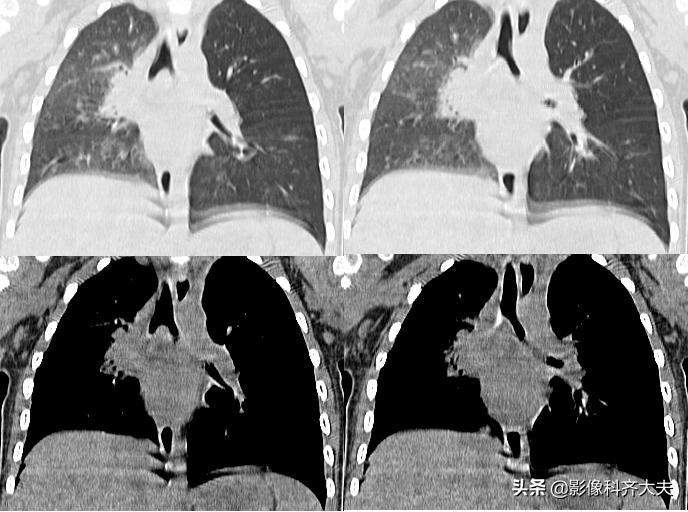

病例7、病史:患儿,女,16个月,吃饭呛咳,来院就诊。(图片来源:邯郸市第一医院)

图中CT轴位扫描及MPR冠状位重建,清晰显示左左侧支气管异物,红色箭头所示。

MinIP(最小密度投影重建)可准确直观显示异物的形态、大小、位置、堵塞程度等各种相关情况。可有效弥补X线胸片和常规CT诊断上的不足,作为支气管镜前筛查和手术定位的重要依据。

MinIP(最小密度投影)对气管、支气管等低密度组织的组织结构较为敏感,可清晰显示气管、支气管的解剖结构,异物情况,气管支气管形态,病变情况等等,效果显著优于X线平片和轴位CT,可为支气管镜取异物提供重要参考。